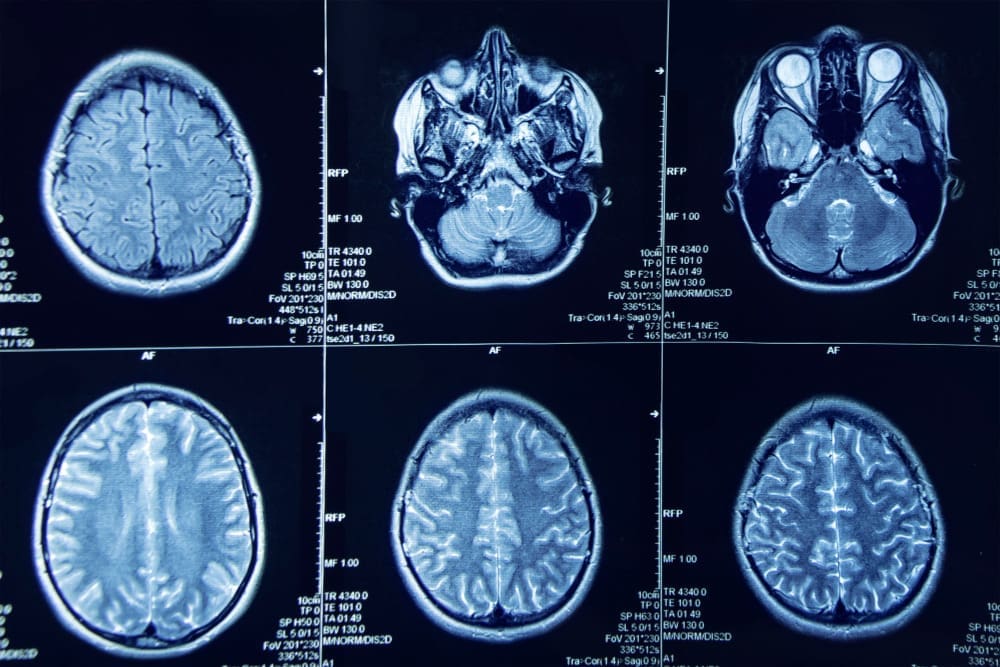

A stroke, or cerebrovascular accident, is a major cause of death and disability. It happens when the brain’s blood supply is cut off. This can be due to a blockage or a vessel rupture. It’s vital to know the signs and symptoms of a stroke to act quickly.

It’s vital to know how serious a fast cerebrovascular accident is. A stroke happens when blood flow to the brain stops or slows down. This means the brain can’t get the oxygen and nutrients it needs. Brain cells can die quickly, often in just minutes to hours.

There are mainly two kinds of strokes: ischemic and hemorrhagic. Ischemic strokes happen when a blood vessel in the brain gets blocked. Hemorrhagic strokes occur when a blood vessel bursts and bleeds into the brain.

Knowing the signs of a stroke is key to getting help fast. A stroke happens when the brain doesn’t get the oxygen and nutrients it needs. Time is of the essence because the brain starts to die quickly.

Acting fast when a stroke happens can save brain cells and lives. Every minute counts because without blood flow, brain damage grows. Quick treatment with clot-busting drugs can help a lot.